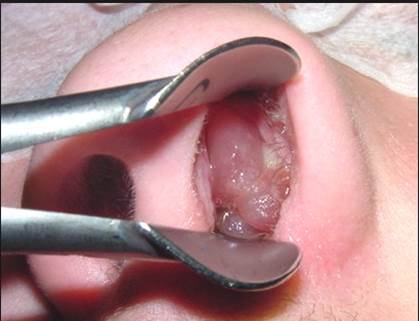

What type of procedure is this?

Caldwell Luc’s operation (maxillary sinus drainage surgery)